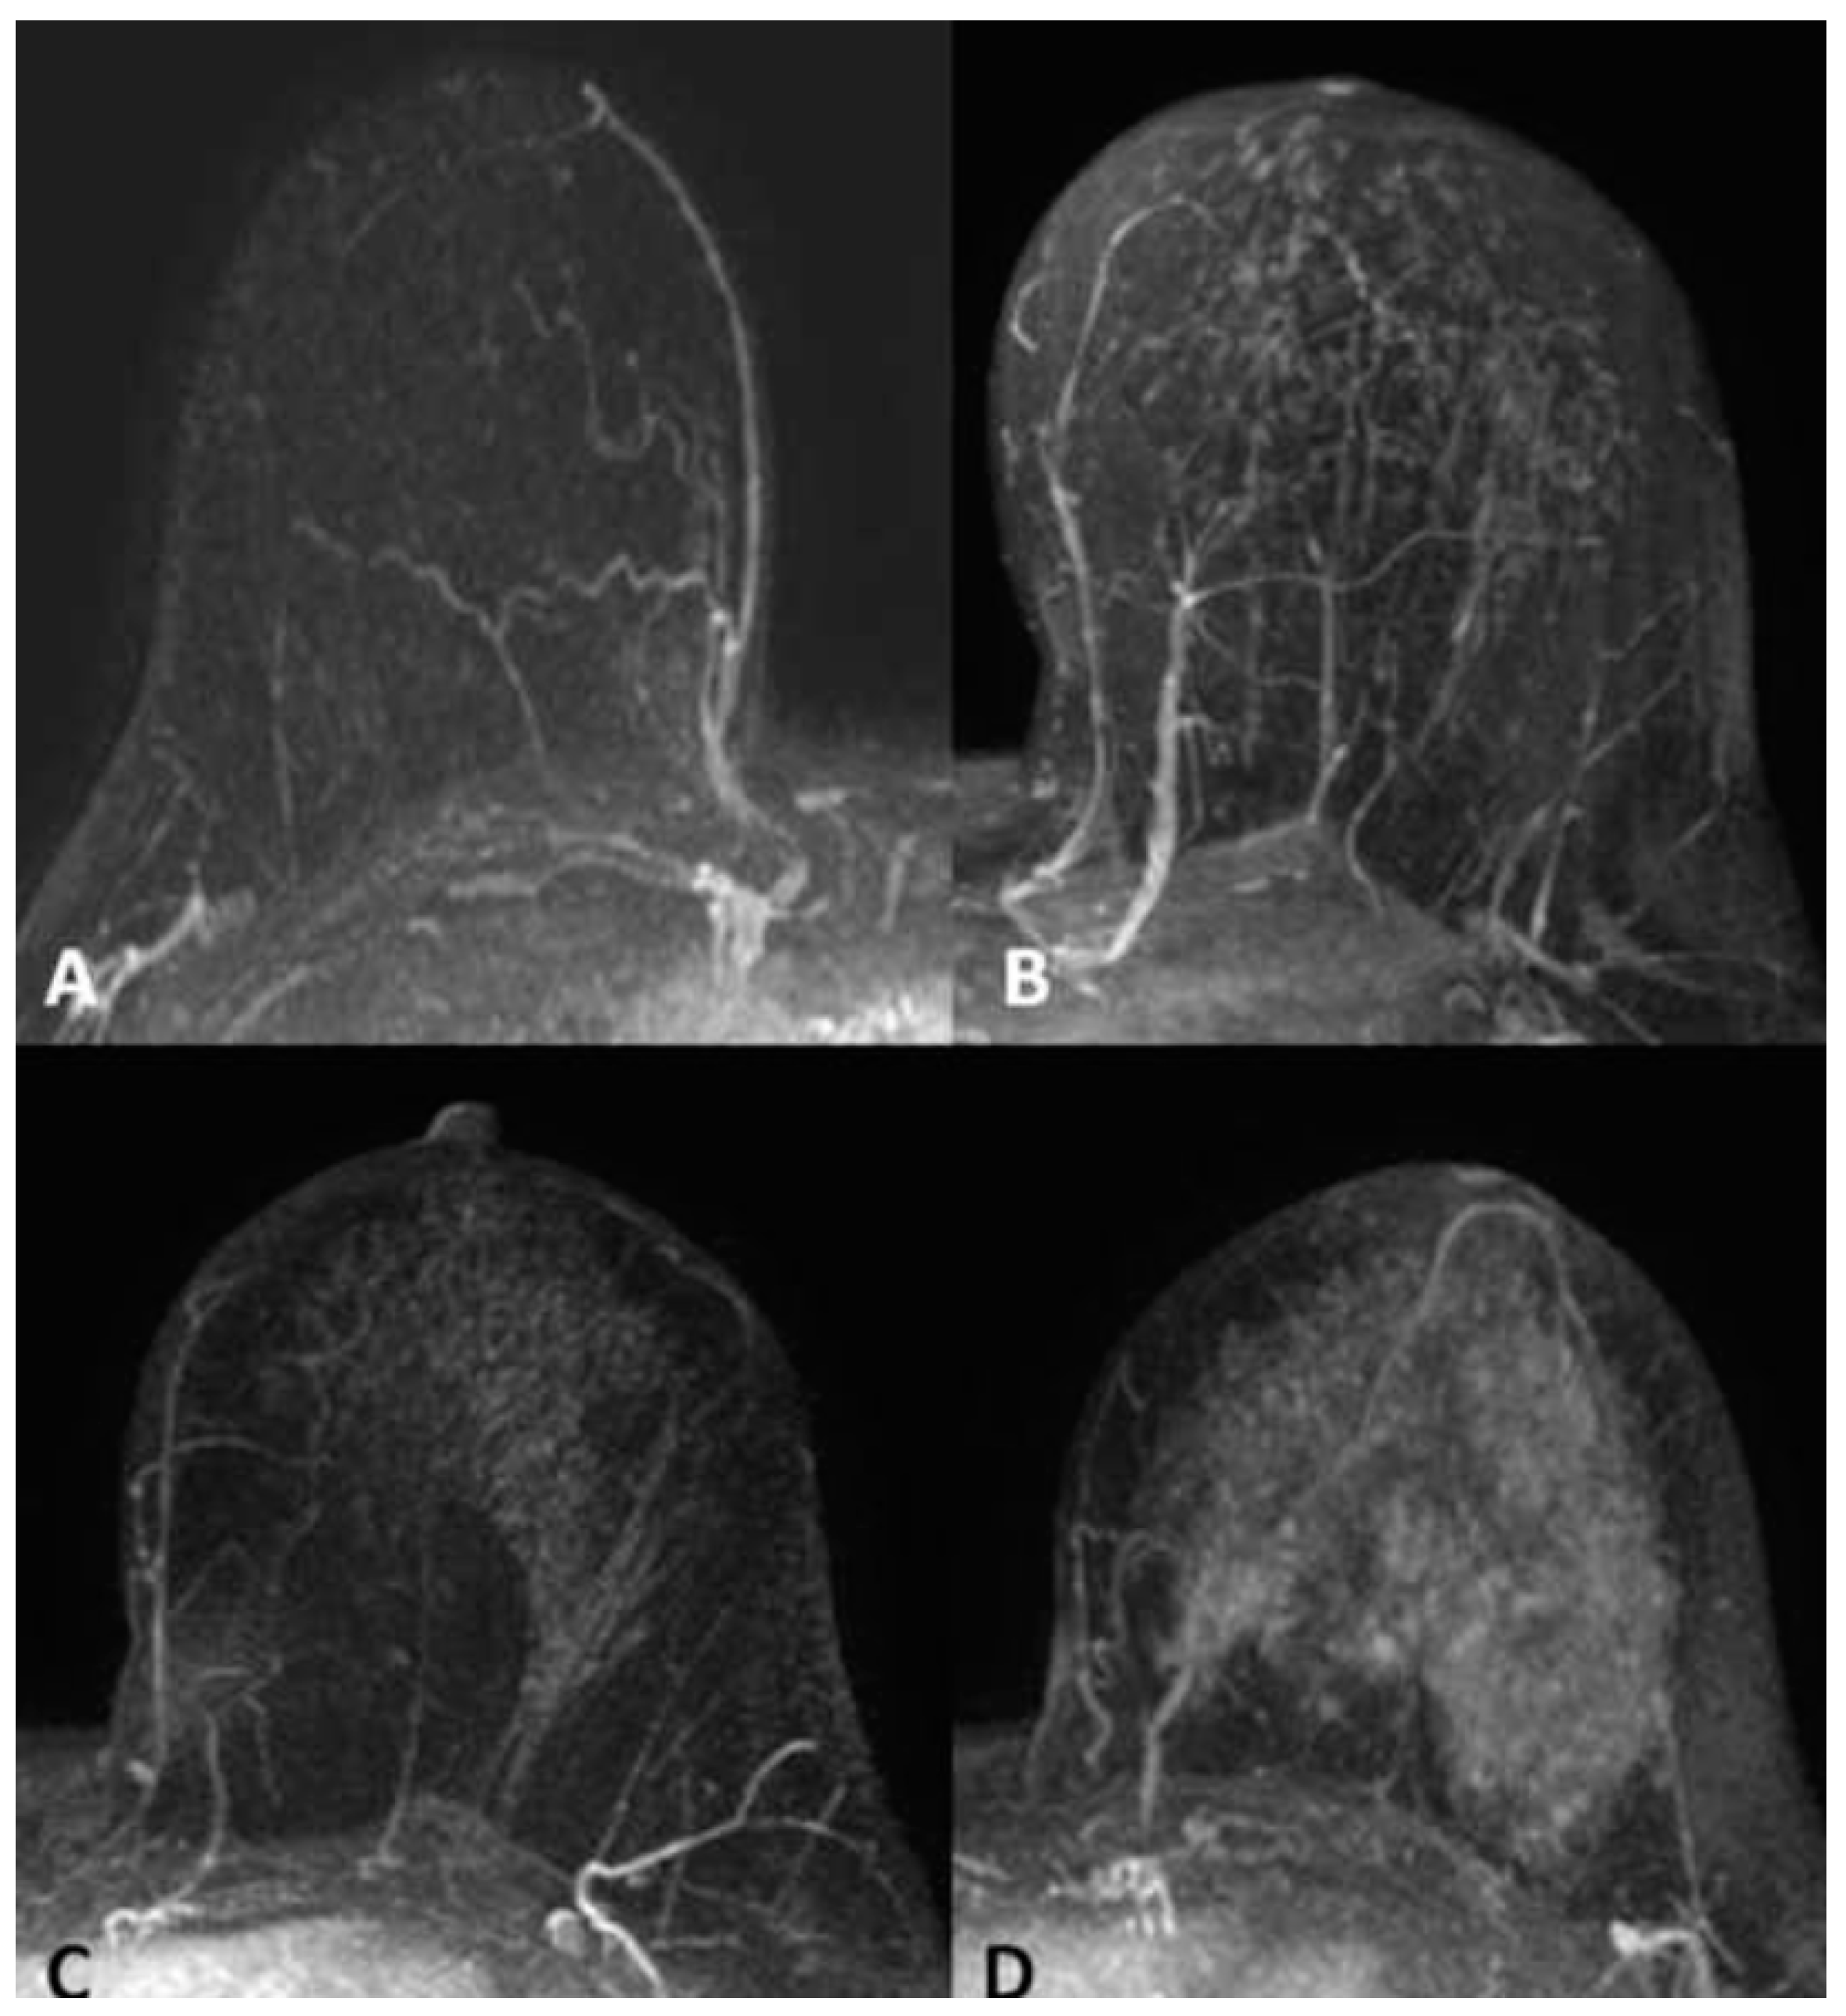

- Background Parenchymal Enhancement (BPE): The degree of normal breast tissue enhancement after gadolinium contrast administration was measured using MRI. BPE was classified into the following four categories: minimal (Type 1), mild (Type 2), moderate (Type 3), and marked (Type 4);

- Breast MRI Findings: MRI was used to evaluate breast tissue characteristics, including BPE and the presence of any abnormal lesions or malignant findings. The MRI sequences included T1-weighted imaging, T2-weighted imaging, dynamic contrast-enhanced imaging, and subtraction imaging for detecting enhancing lesions.